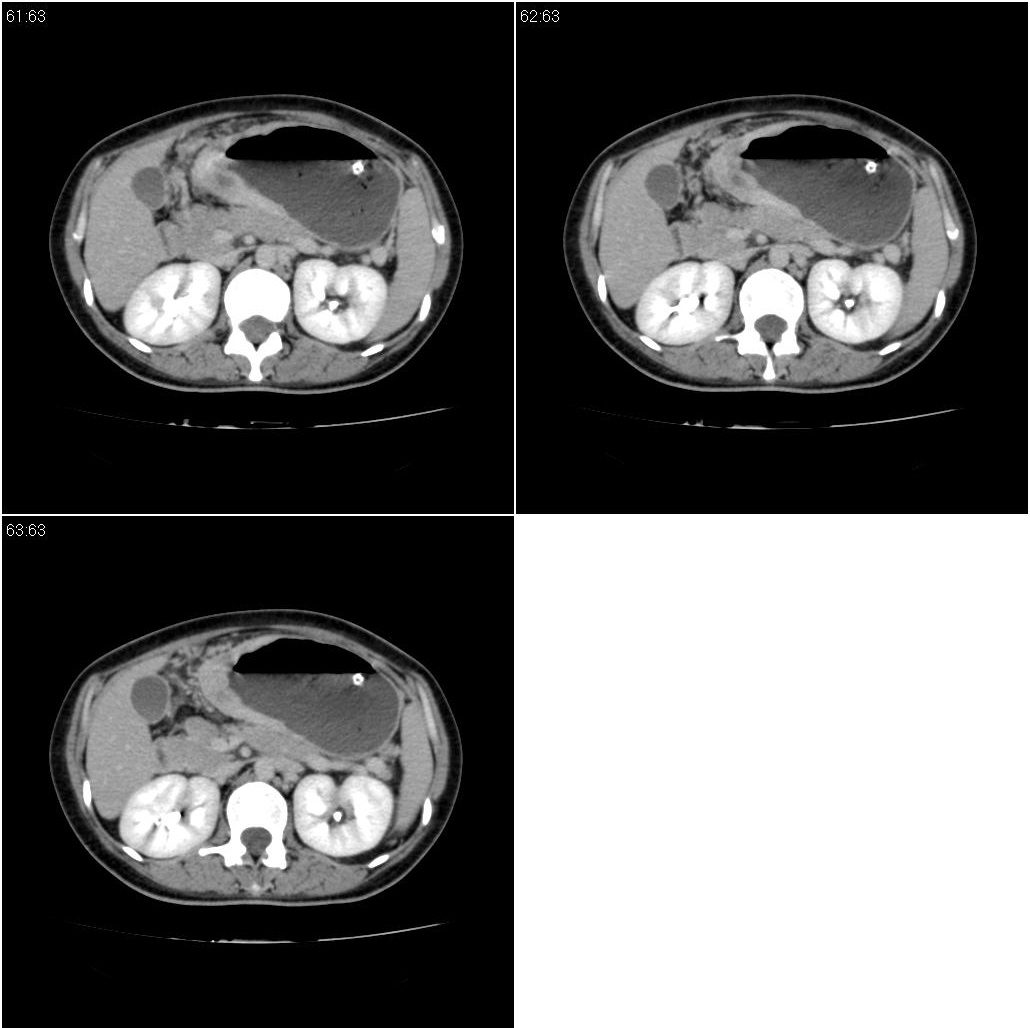

标题: CT21386:女性,33岁。4个月前因妊娠发现盆腔肿物。 [打印本页]

女性,33岁。4个月前因妊娠发现盆腔肿物。ca-125: 1100

考虑胃癌伴腹腔内淋巴结转移。

胃壁局限性增厚,支持肿瘤性病变伴周围脓肿形成可能

未见明显肿大淋巴结,另肝脾大

支持;胃癌【浸润】幽门梗阻.胰头、胆囊及肝左叶受侵,副脾.

考虑胃窦占位并肝门部淋巴结转移

考虑胃窦部胃癌伴小弯侧和腹腔淋巴结转移。